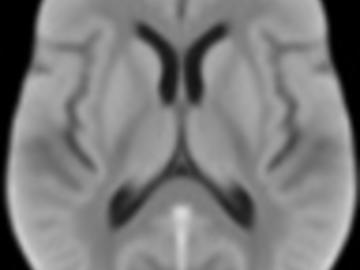

Normative brain atlases are a standard tool for neuroscience research and are, for example, used for spatial normalization of image datasets prior to voxel-based analyses of brain morphology and function. Although many different atlases are publicly available, they are usually biased with respect to an imaging modality and the age distribution. Both effects are well known to negatively impact the accuracy and reliability of the spatial normalization process using non-linear image registration methods. An important and very active neuroscience area that lacks appropriate atlases is lesion-related research in elderly populations (e.g. stroke, multiple sclerosis) for which FLAIR MRI and non-contrast CT are often the clinical imaging modalities of choice. To overcome the lack of atlases for these tasks and modalities, this paper presents high-resolution, age-specific FLAIR and non-contrast CT atlases of the elderly built from clinical images.

We provide an asymmetric and symmetric version of both the FLAIR and NCCT atlases in the standard MNI coordinate system with binary masks for the brain volume. We also provide the deformation field to map parcellations in the MNI space to our atlases (both symmetric and asymmetric) should researchers require this in their individual research projects.